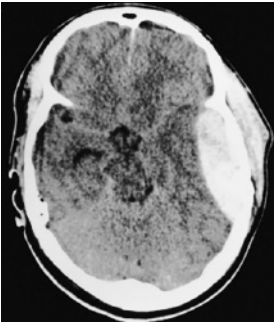

Paciente do sexo masculino, 23 anos, foi vítima de acidente

automobilístico no qual o veículo em que estava colidiu com

caminhão. Usava cinto de segurança e foi retirado consciente

do carro pela equipe de resgate. Apresentava amnésia

anterógrada. Após atendimento pré-hospitalar, o paciente foi

levado ao pronto-socorro, sem déficits motores ou sensitivos.

No hospital, o médico pede uma tomografia computadorizada

de crânio para avaliação. Alguns minutos depois, a equipe de

enfermagem solicita avaliação de emergência para o paciente,

com necessidade de intubação orotraqueal por rebaixamento do

nível de consciência e anisocoria com pupila esquerda dilatada.

Tomografia computadorizada de crânio sem contraste

Ao considerar a situação clínica do paciente e a imagem

tomográfica apresentada, o médico diagnosticou